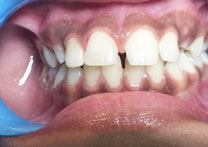

After Treatment

Patient with a complaint of rotated upper left lateral incisors. Veneers placed for the treatment of the rotated upper left lateral incisors.